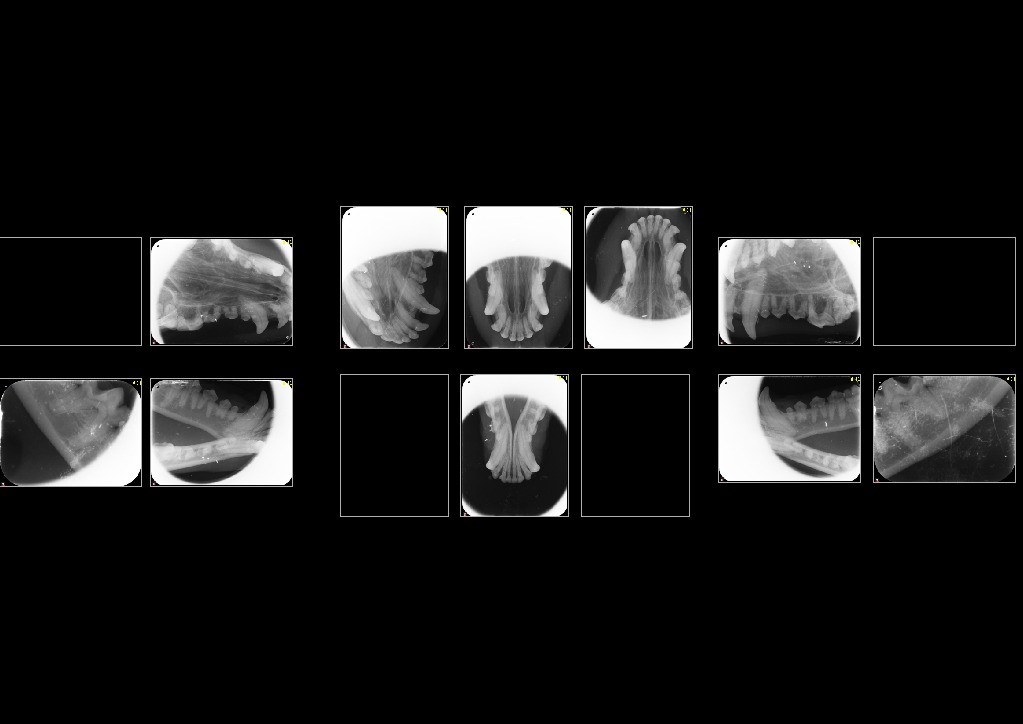

2. 全口牙科 X 光拍攝 (Dental Radiographs)

• 約 60-70% 的牙科問題(如牙根膿腫、齒吸收、牙周骨流失)藏在牙齦下,肉眼看不見,必須靠 X 光診斷。

X-ray images of human teethAI-generated content may be incorrect.

犬牙科X光紀錄